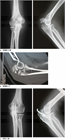

1. 定期レビューを行い、肘頭脱臼骨折をolecranon fracture dislocation (OFD)に変更した。その根拠についても記載した。

前者に対しては観血整復内固定術が行われることが多く、tension band wiring、intramedullary screw fixation、肘頭用アナトミカルロッキングプレートによるプレート骨接合術などの選択肢がある。